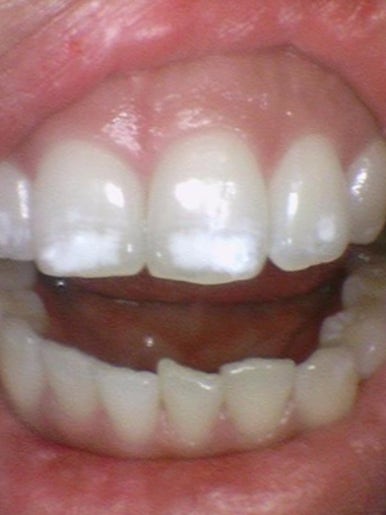

화이트스팟 레진치료시 삭제정도

화이트스팟으로 치아 삭제한 정도는 위 사진과 같습니다.

물론 깊을수록 많이 삭제되겠지만 겉부분만 어느정도 삭제한다고 보면 될 것 같아요.